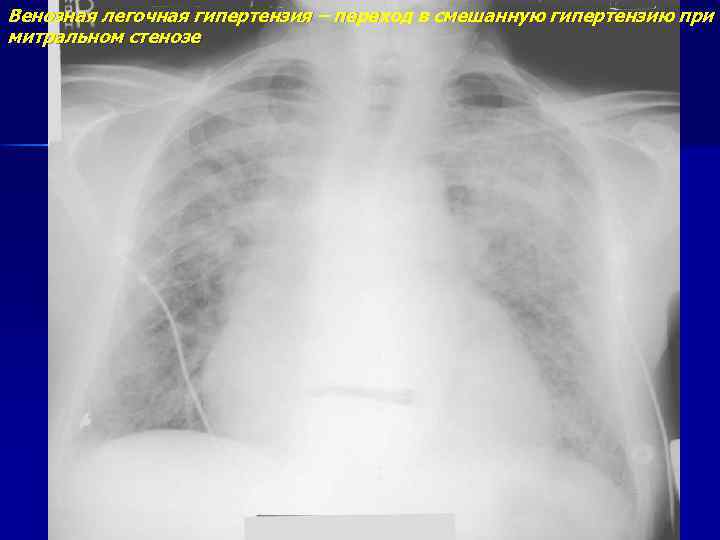

Венозная легочная гипертензия – переход в смешанную гипертензию при митральном стенозе